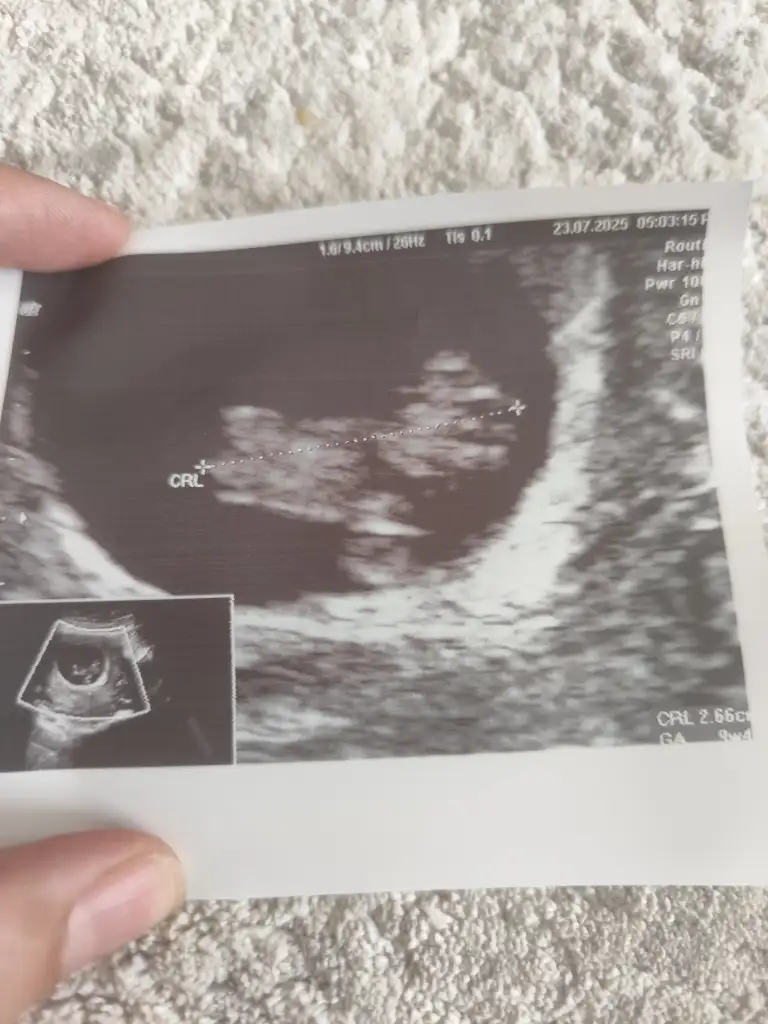

Ay bence kız10+2 karından ultrason bana da bakar mısınız lütfen aşırı merak ediyorum

Bizede bakarmisiniz10+2 karından ultrason bana da bakar mısınız lütfen aşırı merak ediyorum